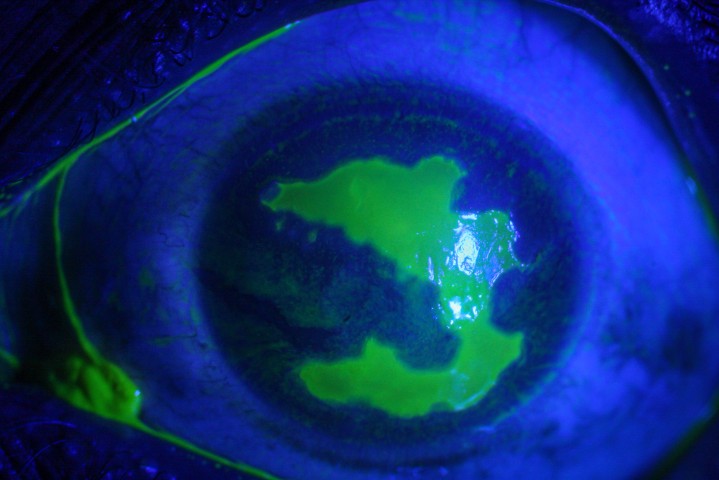

Always check carefully for necrotising scleritis as this can be subtle in the early stages. If in doubt, it can be useful to look with a green light and also to check for fluorescein staining over the conjunctiva.

Fig. 3 Surgically induced necrotising scleritis following diabetic vitrectomy

Fig. 4 Fungal scleritis with hypopyon